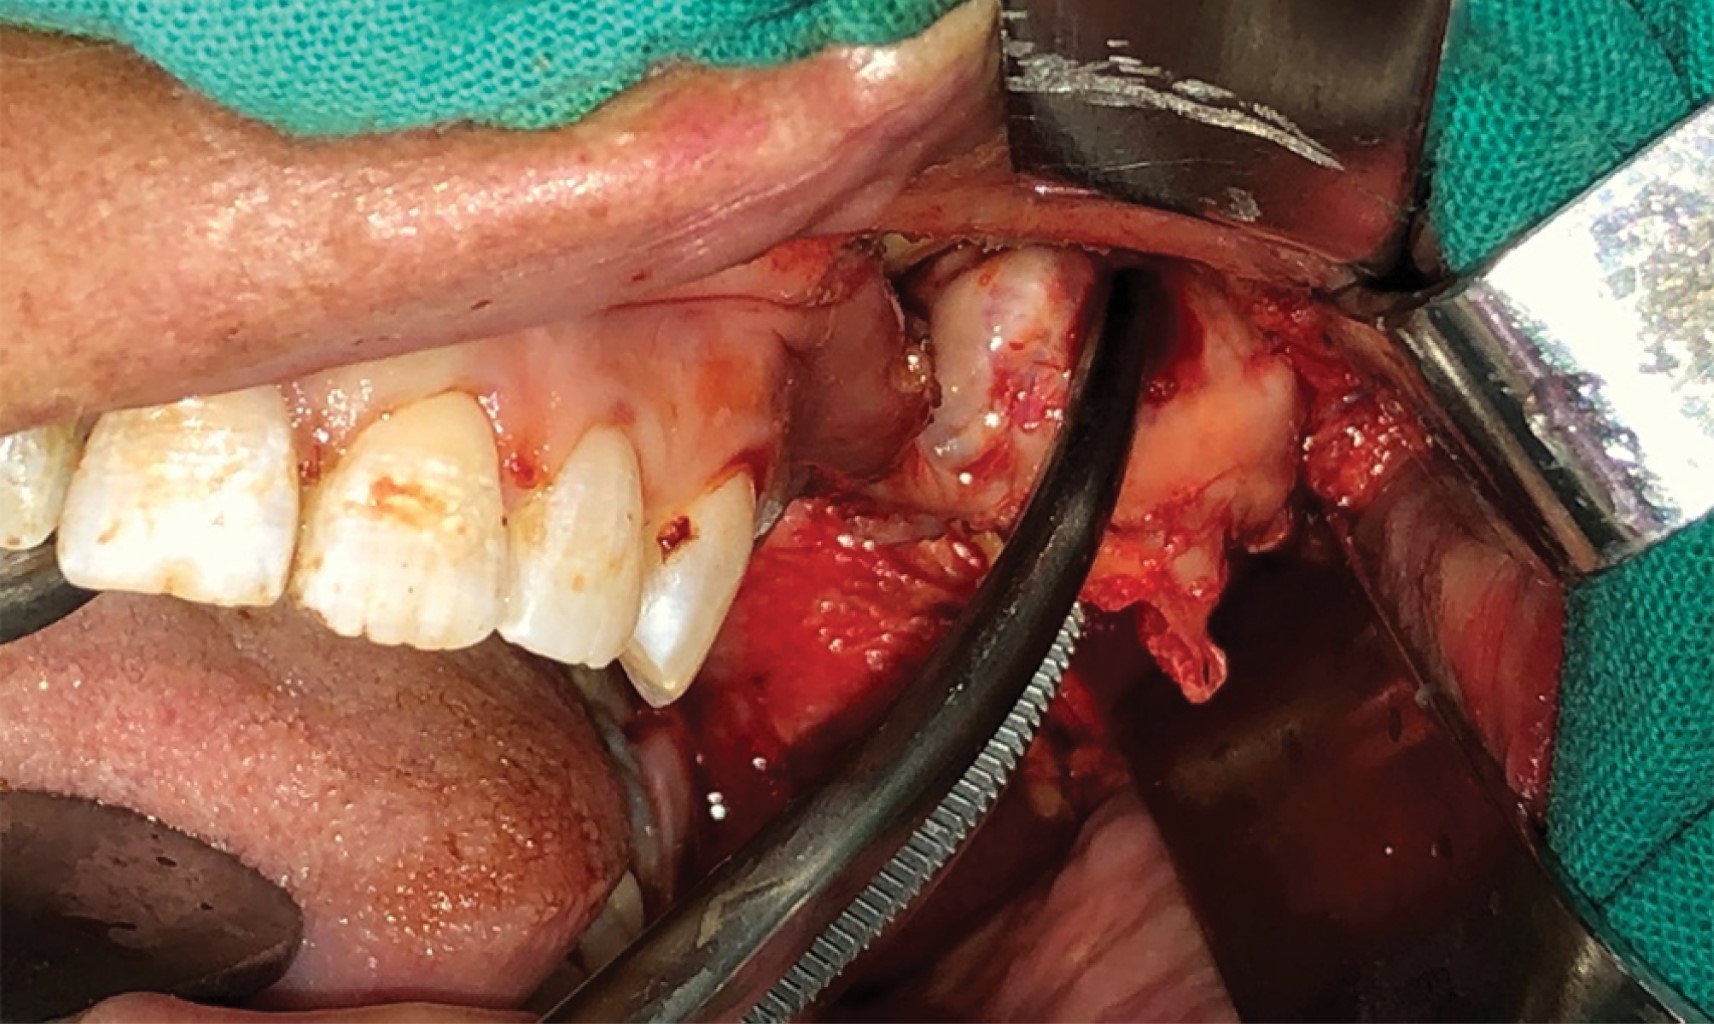

Se realiza tratamiento quirúrgico bajo anestesia general con intubación nasotraqueal y por medio de abordaje intraoral se procedió a la coronoidectomía con instrumental rotatorio, desinserción del músculo temporal y remoción de una masa tumoral con forma de hongo envuelta con un tejido cartilaginoso (Figuras 8 y 9).

El estudio histopatológico informó un fragmento óseo de 2.5 × 5.5 cm que presenta una formación exofítica grisácea firme con superficie externa irregular. Los cortes histológicos muestran tejido cartilaginoso típico superficial con formación ósea trabecular subyacente típica con escasos focos cartilaginosos intratrabeculares. Diagnóstico osteocondroma (Figura 10).